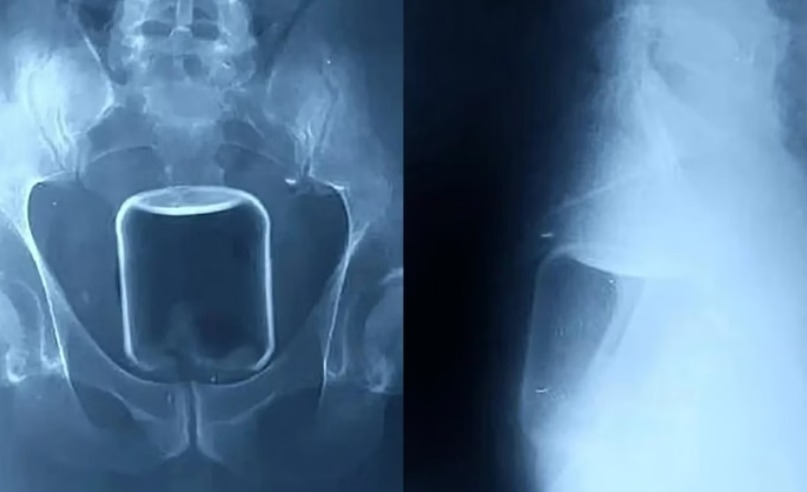

Imagens de raio-X divulgadas pelo hospital mostram um copo de vidro preso na parte superior do reto, indo em direção ao intestino.